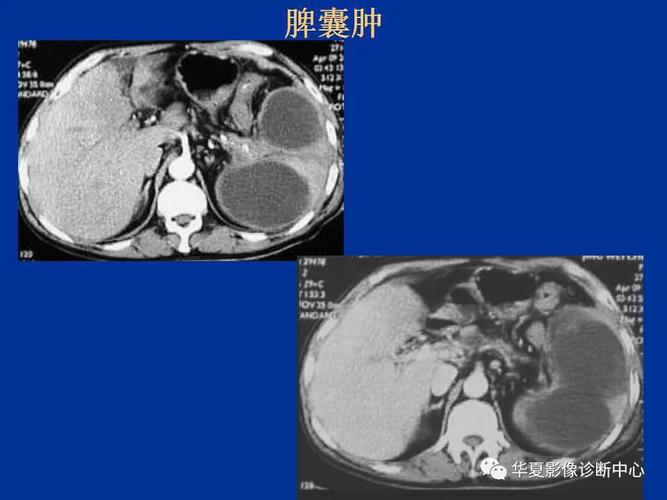

脾脏正常ct及常见疾病影像表现

脾脏疾病的ct诊断